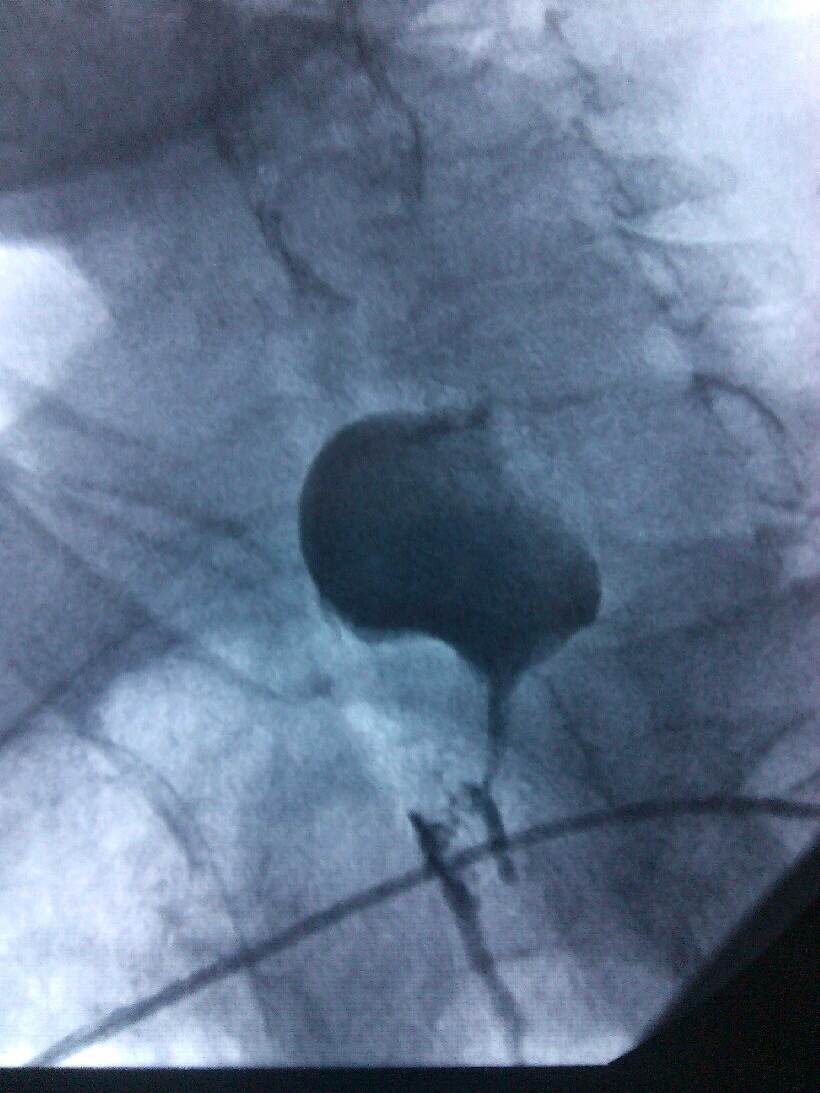

根据病人的的身体条件,无法采用手术、放疗、化疗进行治疗。肿瘤科主任、副主任医师熊小平组织医生详细分析患者的病情,找到病因所在,制定周密的治疗方案,运用食管支架植入法将食管扩张,这样既解决了患者的“吃饭”问题,又解决了分泌物排流的问题,减轻了患者的痛苦,提高了生活质量。患者及家属非常感激,多次口头表示感谢:“没想到51黑料